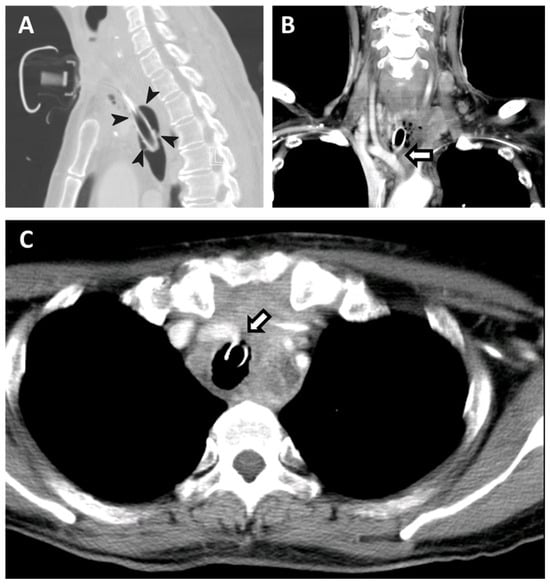

Over-Inflating a Tracheostomy Tube Cuff for Tracheo-Innominate Artery Fistula